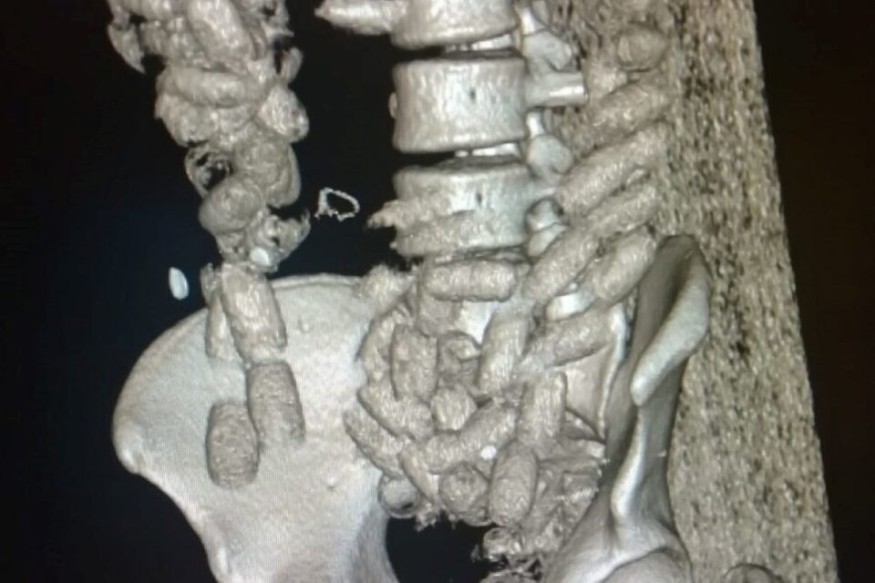

Le « tuyau » n’était pas percé puisque cet homme originaire de Saint-Laurent-du-Maroni, d’une petite trentaine d’années, conduit sous bonne garde à l’hôpital, a expulsé de son estomac une centaine d’ovules de cocaïne. L’équivalent d’1 kg de produit, pur à 90%.